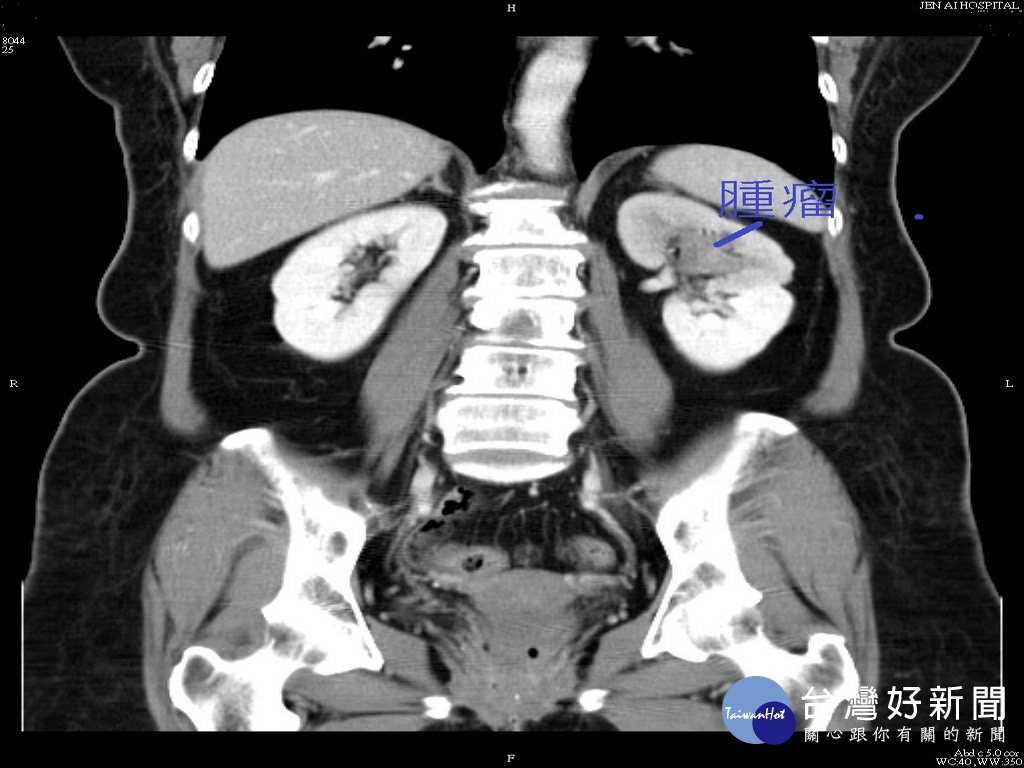

婦人無痛性血尿 確診左腎盞泌尿道上皮細胞癌

患者膀胱腫瘤。林重鎣翻攝

53歲周阿姨,肉眼可見血尿已斷斷續續超過2星期, 但無小便疼痛及任何不適感。 因極為焦慮而在子女陪同下前往大里仁愛醫院泌尿科門診就診, 接受顯影劑尿路攝影、膀胱鏡、電腦斷層及輸尿管鏡的切片檢查後, 確診為左腎盞泌尿道上皮細胞癌。

大里仁愛醫院泌尿科主任劉緯陽表示, 近期單純無痛性血尿來門診就醫的民眾顯著增多, 雖然沒有其他腰痛、頻尿、急尿不適等明顯症狀的, 但千萬不可輕忽。造成血尿的原因可能來自泌尿系統的任何一個部份 ,包括常見的尿路結石及泌尿道感染都是致病原因, 但是中老年人因無痛性血尿而被診斷為膀胱癌或腎臟、 輸尿管尿路上皮細胞癌的患者為數不少。

泌尿科劉醫師提醒,膀胱癌或尿路上皮癌最常發生在四十歲以上的民 眾,男、女都會發生,且無季節之分, 通常症狀只有無痛性血尿表現。如果有抽煙病史、 曾有接觸過化學物質包括農藥、油漆等致癌物…等致癌因子, 尤其是洗腎患者,若有無痛血尿,好發膀胱癌或尿路上皮癌比率又會 比一般人高出許多,千萬不可忽視。

泌尿科劉醫師建議民眾只要發生無痛性血尿就應即早至泌尿科接受進 一步檢查,以免延誤病情。而53歲周姓阿姨確診為左腎盞泌尿道上 皮細胞癌後,接受腹腔鏡手術切除腎、輸尿管後, 目前門診追蹤復原狀況良好。